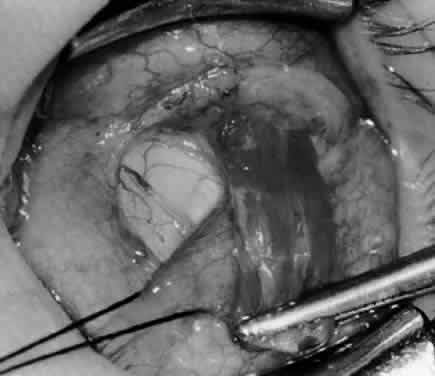

Fig. 5. The Stevens hook is placed adjacent to the posterior edge of the inferior oblique muscle and rotated as the inferior oblique muscle is drawn into the operative field. A forceps is used to retract the redundant Tenon's capsule, encapsulated fat, and intermuscular septum as the muscle is drawn further into the operative field with the Stevens muscle hook.

Fig. 6. The Westcott scissor is used to open the intermuscular septum along the posterior border of the inferior oblique muscle. Care is taken to cut adjacent to the tip of the Stevens muscle hook. This incision is important because it helps to avoid damaging the Tenon's capsule and releasing fat, which leads to the adherence syndrome and postoperative hypotropia.